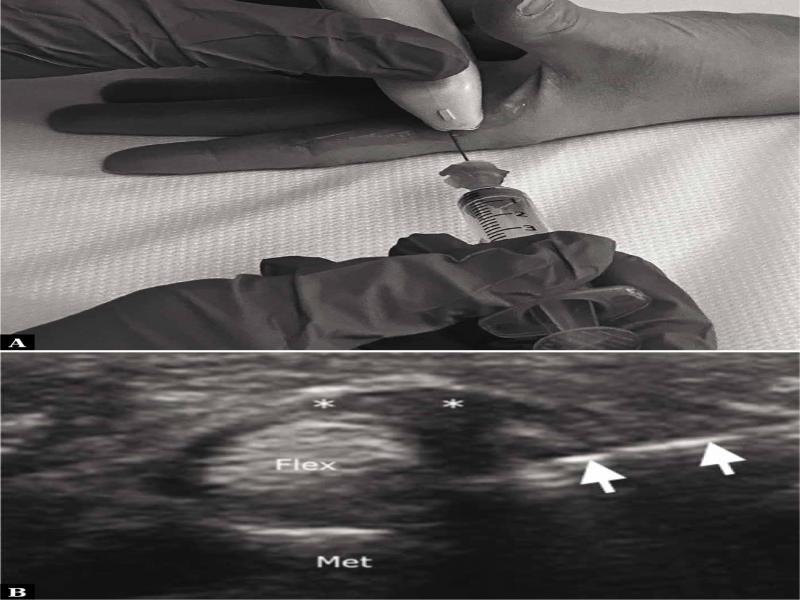

Fig. 2.